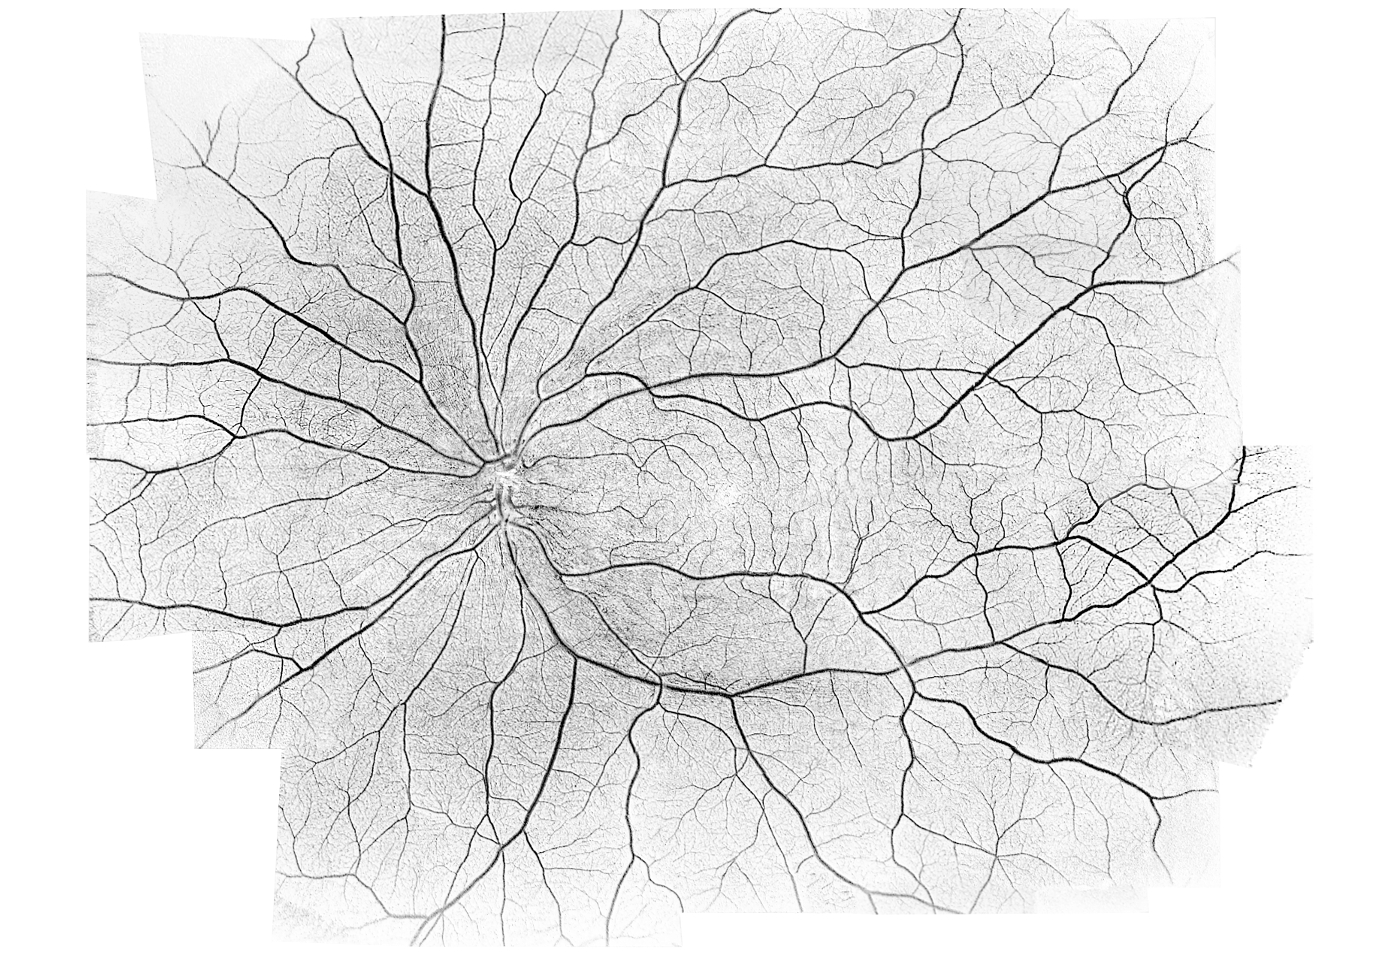

- Mosaik-Funktion

Mosaik-Scan-Bereiche:

- Vordefinierte Auto-Bereiche: 10 x 6 mm, 12 x 5 mm, 7 x 7 mm, 10 x 10 mm

- Manueller Bereich bis 18 x18 mm

Angio-Mosaik Auswertungen:

- Vaskulär und Enface: Vitreous, Superficial, RCP, Deep, Outer, Choriocapilaries, Choroid, Custom